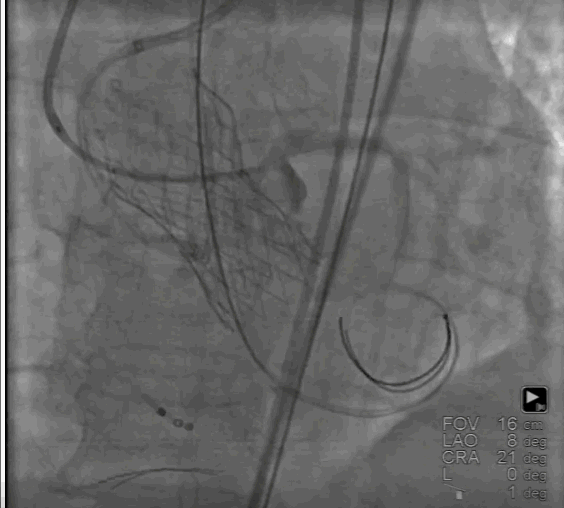

按照预先制定手术策略,首先,周玉杰教授内科团队首先进行左右冠脉保护,然后进行超硬导丝跨瓣进,23mm快速起搏预扩,左右冠脉均无显影,证实冠脉预先评估无误,选择右冠脉居中体位释放,利用瓣膜底部与无冠猪尾导管定位,快速起搏开始释放,释放至限位,由于是可回收系统进行多次反复观察评估冠脉情况,释放位置稳定较好,确认冠脉无风险完全释放瓣膜,撤出体外。